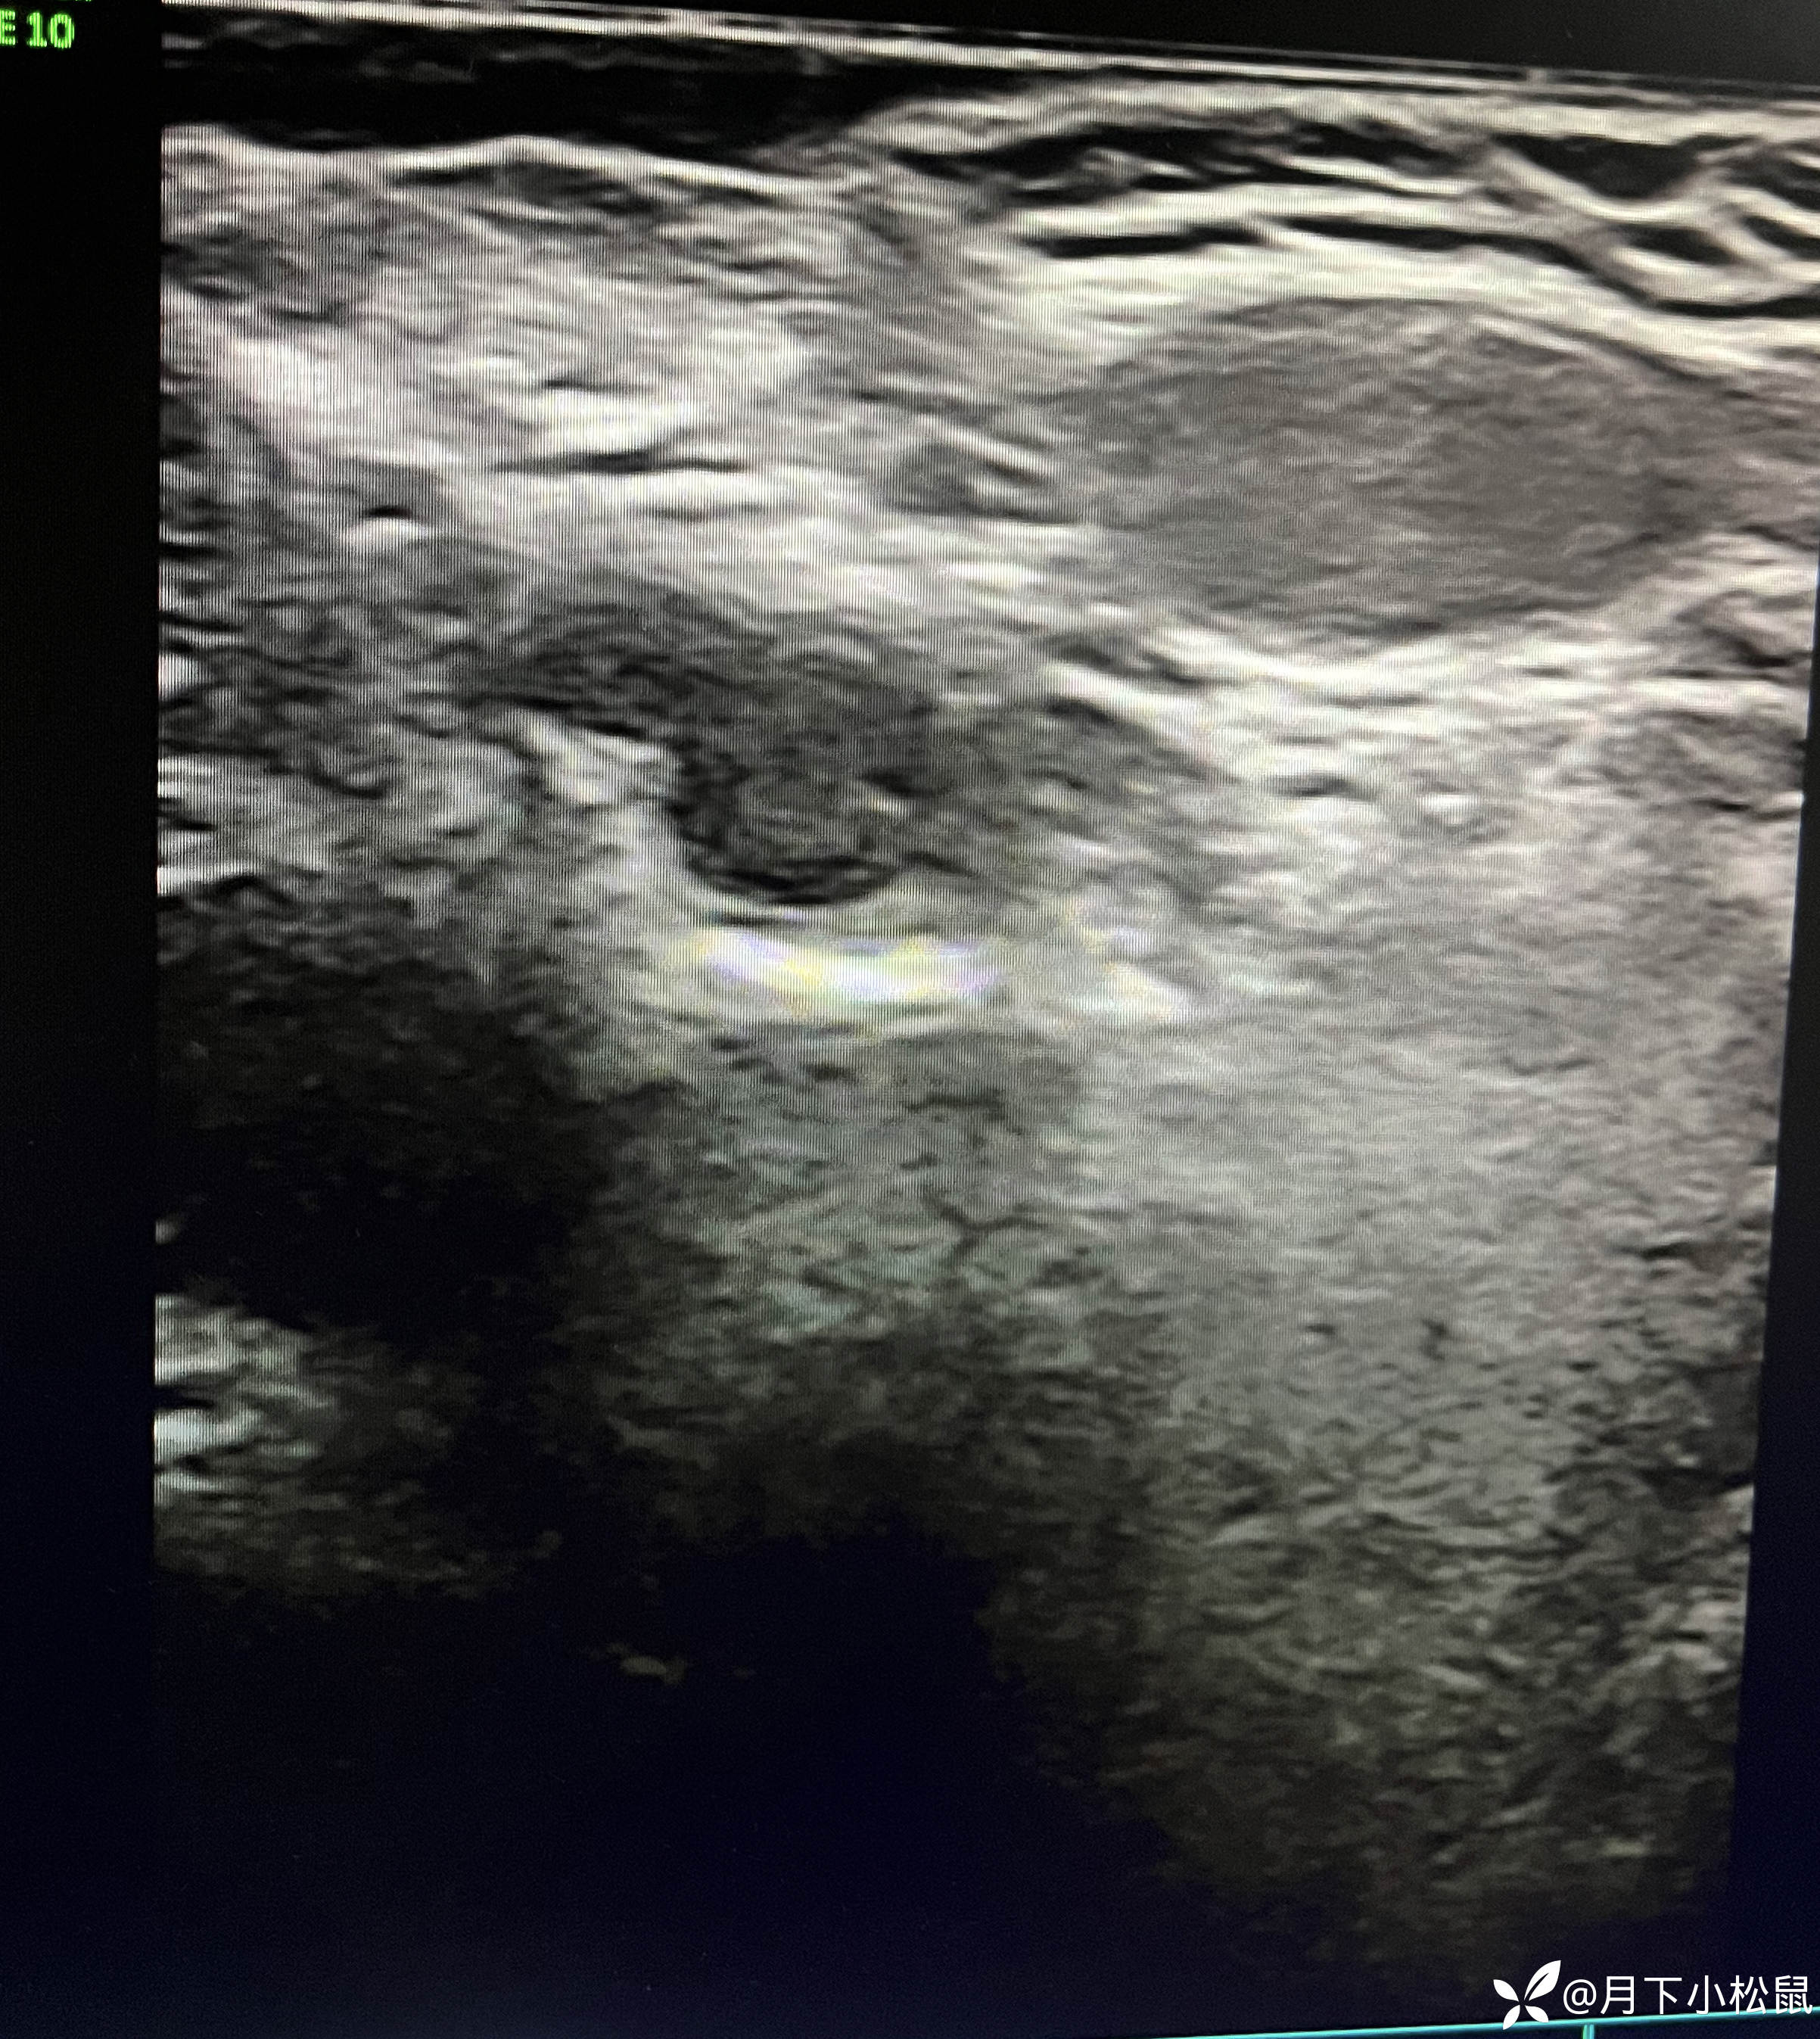

给开了B超,申请单上面写了详细的体格检查内容,同时嘱家属在做B超时一定和做B超的医生说仔细看看蛋蛋。

腹部B超检查报告回报示:

报告: